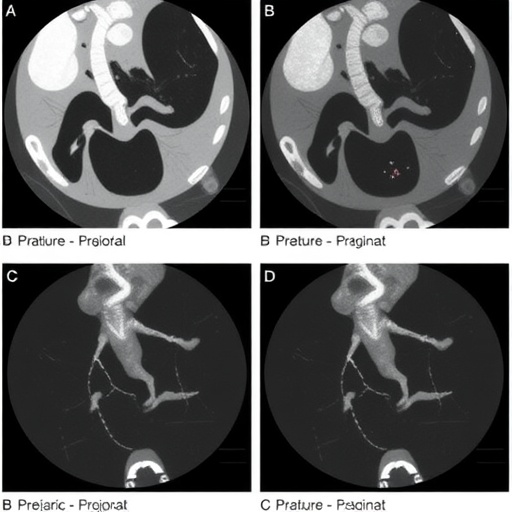

Endoscopic retrograde cholangiopancreatography involves the use of endoscopy to visualize the bile ducts and pancreatic ducts. This minimally invasive technique allows for both diagnostic imaging and therapeutic interventions. The flexibility of ERCP makes it a compelling choice for patients who are not suitable candidates for more invasive surgical options, a common scenario in pediatric cases due to various factors, including the child’s age and underlying health conditions.